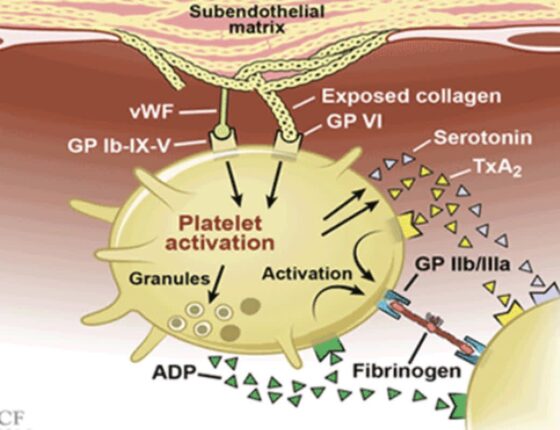

항혈소판제 작용 종류 사용법 및 주의사항